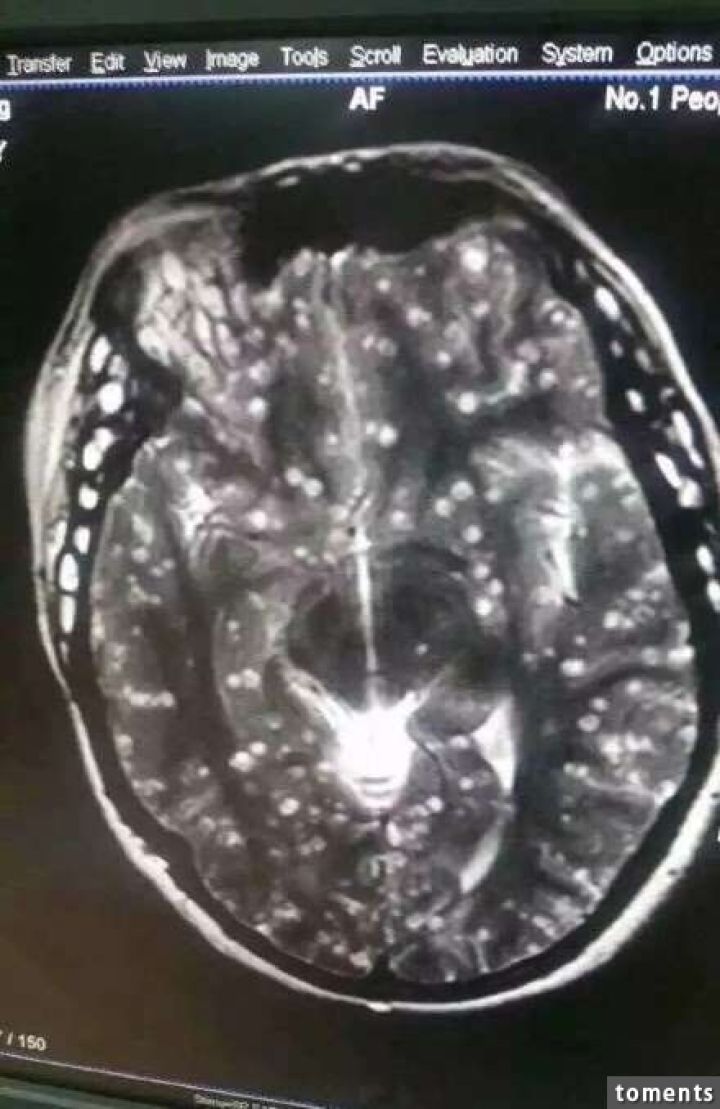

病院では頭部MRIと全身CTスキャンが行われたが、その検査結果は専門家さえも驚く衝撃的なものだった。それもそのはず、女性の全身はすでに無数の寄生虫に侵されており、大脳や顔面の筋肉にさえも感染が見られるひどい有様だったからだ。

医師の話では、女性の体内の寄生虫の一部はすでに死に、石灰化しており、全身の痛み以外に眼球突出や網膜出血といった症状も見られたとのこと。治療はすぐに行われたものの、一部の寄生虫は体外に排出されず、女性には後遺症が現れる可能性も否めないという。